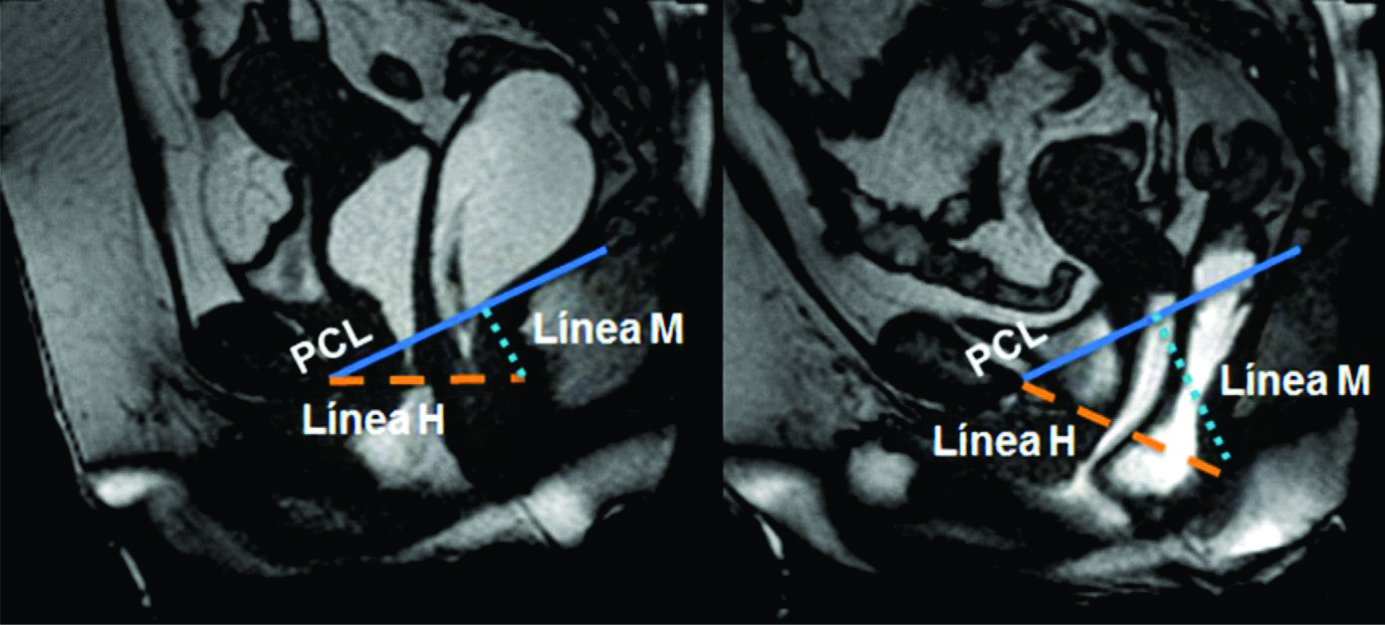

Figura 4

Línea H y línea M.Imágenes potenciadas en T2 de alta resolución en el plano sagital. Se observa el cambio en el valor que adopta la línea M y la línea H al comparar el reposo frente a la defecación. Según sus medidas en centímetros, se puede graduar en cuatro estadios diferentes.

La línea H se traza desde el borde inferior del pubis hasta la pared posterior del recto a la altura de la unión ano rectal, representando el diámetro anteroposterior del hiato urogenital, con un valor normal menor a 6 cm (Ver figuras 4).

La línea M es perpendicular a la PCL a nivel del sector más posterior de la línea H y representa el descenso del hiato del elevador, con un valor normal menor a 2 cm. El ángulo ano rectal es el ángulo entre el eje central del canal anal y la pared posterior del recto, con un valor normal entre 108º y 127º y una variación de hasta 15º en Valsalva.

Además se debe valorar la relajación del piso pélvico, a través del valor que adquiere tanto la línea H (apertura del hiato urogenital) como la línea M (descenso del piso pélvico) durante las maniobras dinámicas (Ver tabla 4) (7).